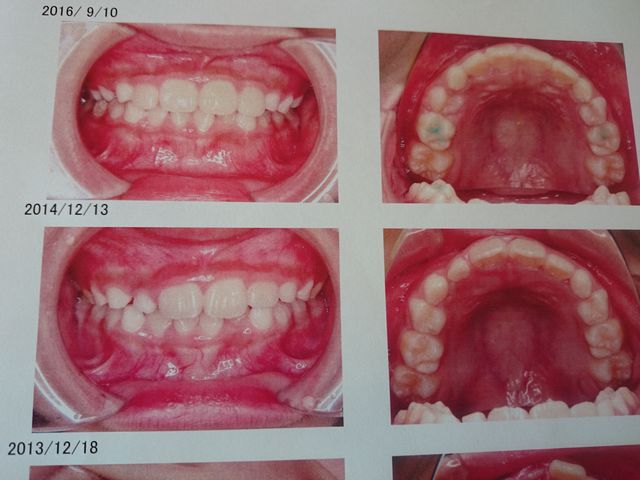

矯正歯科に行きました。二人とも少しずつよくなっています。《とり》は上の前歯四本につけていたワイヤーを外しました。

矯正しているので、だんだんきれいになってきています。